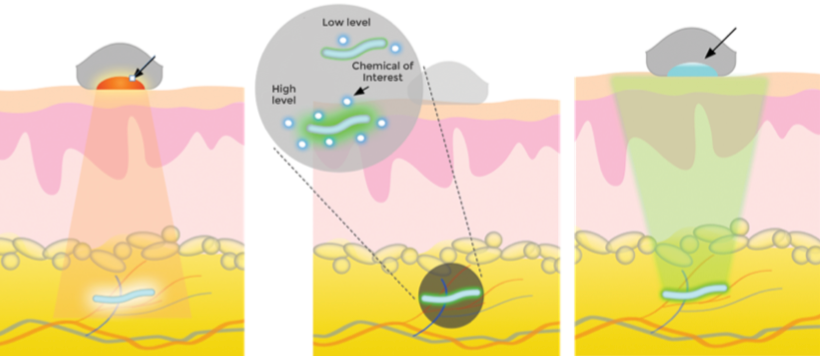

Left: Infrared light (arrow shows excitation light) causes a biosensor (blue) under the skin to fluoresce at a level determined by the chemical of interest (center). Right: A detector (arrow) receives and analyzes the signals from the biosensor and transmits data to a computer or phone. (credit: Profusa)

A technology for continuous monitoring of glucose, lactate, oxygen, carbon dioxide, and other molecules — using tiny biosensors that are placed under the skin with a single injection — has been developed by DARPA/NIH-supported Profusa. Using a flexible, biocompatible hydrogel fiber about 5mm long and 0.5mm wide, the biosensors can continuously measure body chemistries.

An external device sends light through the skin to the biosensor dye phosphor, which then emits light proportional to the concentration of the current analyte (such as glucose) of interest. A detector then wirelessly transmits the brightness measurement to a computer or cell phone to record the change. Data can be shared securely via digital networks with healthcare providers.

To date, the injected biosensors have functioned for as long as four years. For example, tracking the rise and fall of oxygen levels around muscle with these sensors produces an “oxygen signature” that may reveal a person’s fitness level.

Until now, local inflammation and scar tissue from the “foreign body response” (from a sensing electrode wire that penetrates the skin) has prevented development of in-body sensors capable of continuous, long-term monitoring of body chemistry. The Lumee Oxygen Platform, the first medical application of the biosensor technology, was approved in 2017 for sale in Europe, designed for patients undergoing treatment for chronic limb ischemia, avoiding amputations. — Profusa